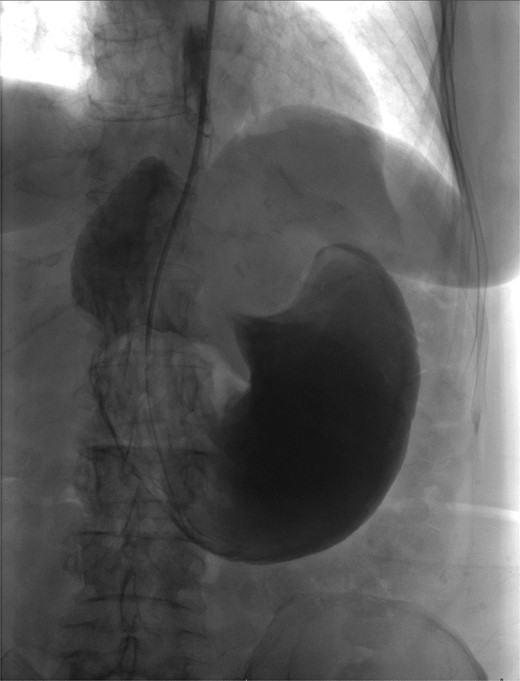

The patient was a 74-year-old female with a history of hypertension, chronic migraines, hiatal hernia repair with Nissen fundoplication repair, and cecal volvulus treated with right hemicolectomy who presented with abdominal pain, nausea, and vomiting. Six months prior, she exhibited symptoms of bloating and nausea, which were treated with oral Reglan with some improvement. She reported vomiting episodes for 2 months that acutely worsened over the 4 days prior to presentation. Examination revealed a soft and mildly distended abdomen with tenderness in the epigastrium and left upper quadrant. Initial vital signs showed a temperature of 36.1°C, blood pressure of 149/88 mmHg, heart rate of 115 beats/min, and oxygen saturation of 95% on room air; tachycardia resolved with resuscitation. Labs were notable for a white blood cell count of 8.8 × 1000/mcL and hemoglobin of 14.2 g/dL. Sodium was 137 mEq/L, potassium was 3.3 mEq/L, and creatinine was 0.75 mg/dL. Computed tomography (CT) of the abdomen and pelvis (Figs 1 and 2) showed gastric volvulus without pneumatosis, significant wall thickening, or distention. Nasogastric tube was placed. An upper gastrointestinal fluoroscopy scan showed no passage of contrast beyond the stomach and demonstrated 90° rotation of the stomach (see Fig. 3). The patient underwent surgery that same day.

Sagittal view of CT scan of abdomen and pelvis demonstrating gastric volvulus.